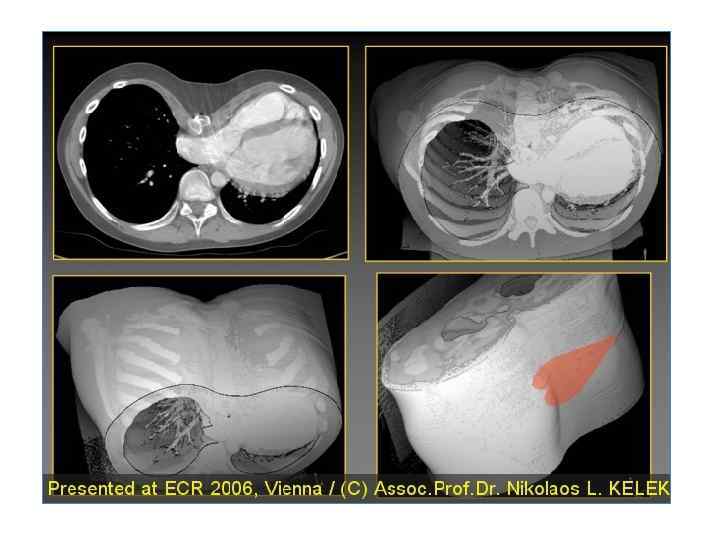

Компьютерная томография • Позволяет получать поперечные срезы тела и с помощью ЭВМ строить объёмные изображения сердца и сосудов • Недостаток метода – довольно высокая лучевая нагрузка